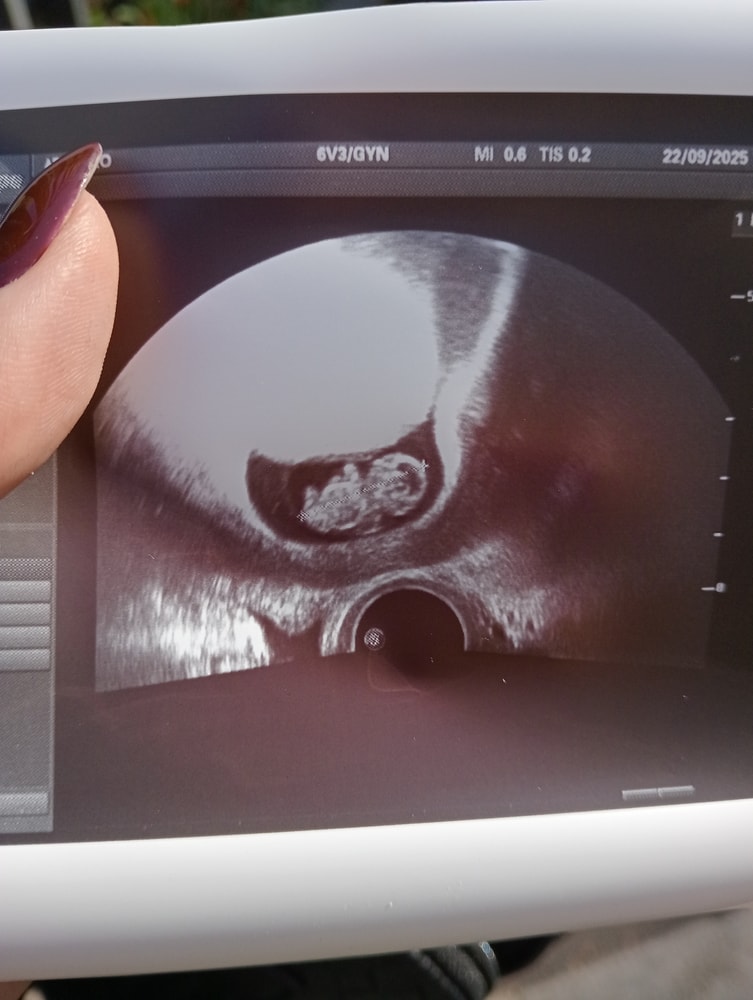

9 недель

УЗИ, КТГ, доплерВот такой уже пупсик на УЗИ😊🤗, репродуктолог сказала что все хорошо, все по сроку, даже показала мне шевеление ручками малыша))) я уже встала на учёт в ЖК, сдала анализы все, уже даже получила молоко и сок для беременных на молочной кухне😂😂😂. Конечно я понимаю что впереди много ещё переживаний, скрининги, сама беременность, но пока я тихонько радуюсь))) родным решили рассказать после 1 скрининга, что бы лишний раз не переживали и меня не дёргали. Слава богу токсикоза практически нет пока, но ужасная сонливость и усталость есть, но работу никто не отменял)))